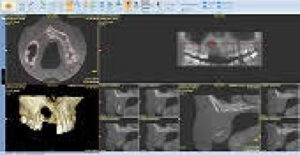

UR8 to UL8

Investigation of cystic lesion in upper right premolar area

KaVo OP 3D Vision V17

8x5cm FOV, 0.125mm voxel size, 120kV, 5mA, 7.4 seconds

There is a large unilocular moderately well-defined radiolucency, 23 x 15 x 14 mm extending from the UR5 apex to the midline but not invading the nasopalatine canal. There is a “through and through” destruction of the buccal and palatal cortical bony plates, as well as destruction of the alveolar bone ridge. The right maxillary sinus and floor of the nose are not involved. There is external root resorption of the UR4.

The lack of bone expansion, resorption of UR4 roots plus the “floating tooth” appearance of UR4 all suggest the possibility of malignancy. In a case such as this an urgent referral to an oral surgeon is recommended for biopsy to determine the diagnosis and rule out a malignancy.